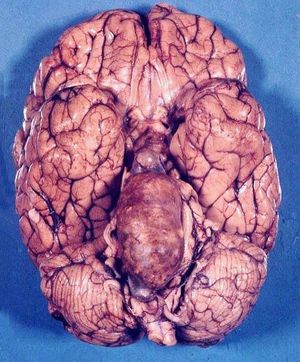

Here you can see basilar artery aneurysm. Acute occlusion of the basilar artery may cause brainstem or thalamic ischaemia or infarction. It is a true neuro-interventional emergency and, if not treated early, brainstem infarction results in rapid deterioration in the level of consciousness and ultimately death.